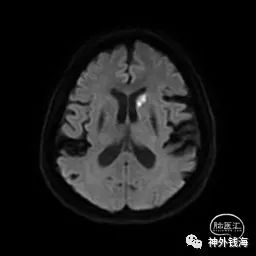

图2 头部磁共振DWI序列可见右侧尾状核头位置急性/亚急性梗塞。说明缺血事件发生时间不长。